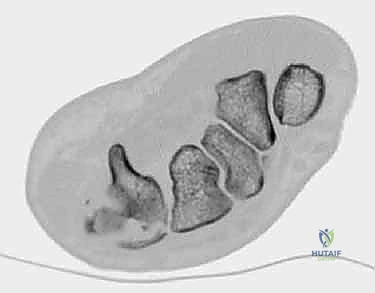

- الأشعة المقطعية (CT Scan): في الحالات المعقدة حيث يكون الكسر مفتتاً أو الخلع متعدداً، يطلب الدكتور أشعة مقطعية ثلاثية الأبعاد (3D CT). هذه التقنية توفر خريطة دقيقة جداً لحجم الشظايا العظمية وتساعد في التخطيط الجراحي بدقة متناهية.

لفهم طبيعة هذه الإصابة، يجب علينا أولاً الغوص في التشريح الدقيق لليد. تتكون اليد من ثلاثة أجزاء عظمية رئيسية:

1. عظام الرسغ (Carpal Bones): وهي 8 عظام صغيرة تشكل قاعدة اليد.

2. عظام المشط (Metacarpal Bones): وهي 5 عظام طويلة تشكل كف اليد.

3. السلّاميات (Phalanges): وهي عظام الأصابع.

مفصل الكربوميتاكاربال هو النقطة التي تلتقي فيها عظام المشط بعظام الرسغ. هذا المفصل ليس متماثلاً في جميع الأصابع: